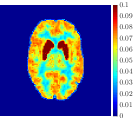

Figure 4, Figure 5, and Figure 6 show the mean images computed over the ten reconstructions obtained by the methods reg-AS-TR, reg-GN, and by the Matlab routine lsqcurvefit implementing a standard Trust-Region-Reflective least-squares algorithm [11, 10]. We used the noise-free IF and the perturbed IF with and of noise, respectively. Figure 7 contains mean and standard deviation values of the kinetic parameters computed over the ten reconstructions and over each one of the four homogeneous regions, for each one of the three noise levels on the IF.

Finally, Figure 8 represents the last frame of the dynamic PET data reconstructed with the mean parametric values returned by reg-AS-TR, reg-GN, and lsqcurvefit, with respect to the noise-free, 10-noise, and 20-noise IFs.

In general, reg-AS-TR and lsqcurvefit seem to provide similar mean reconstructions, although uncertainties associated to lsqcurvefit are significantly bigger. On the other hand reg-GN seems to systematically underestimate the parameter values within region . Furthermore and as expected, for all methods the quality of the parametric reconstructions deteriorates with increasing noise levels; this is more clear from the and parametric images, probably due to the different sensitivities of the data with respect to the model parameters [37]. In reg-GN and lsqcurvefit some artifacts can be observed at the edges of the homogeneous regions, especially around region and region , whereas the effect of regularization in reg-AS-TR results in a reduced presence of artifacts while the structure of the regions is preserved. This general trend is confirmed by the error-bar plots of Figure 7. Finally, the frames in Figure 8 corresponding to reg-AS-TR show a significant improvement of the image quality with respect to what is provided by the other two approaches.